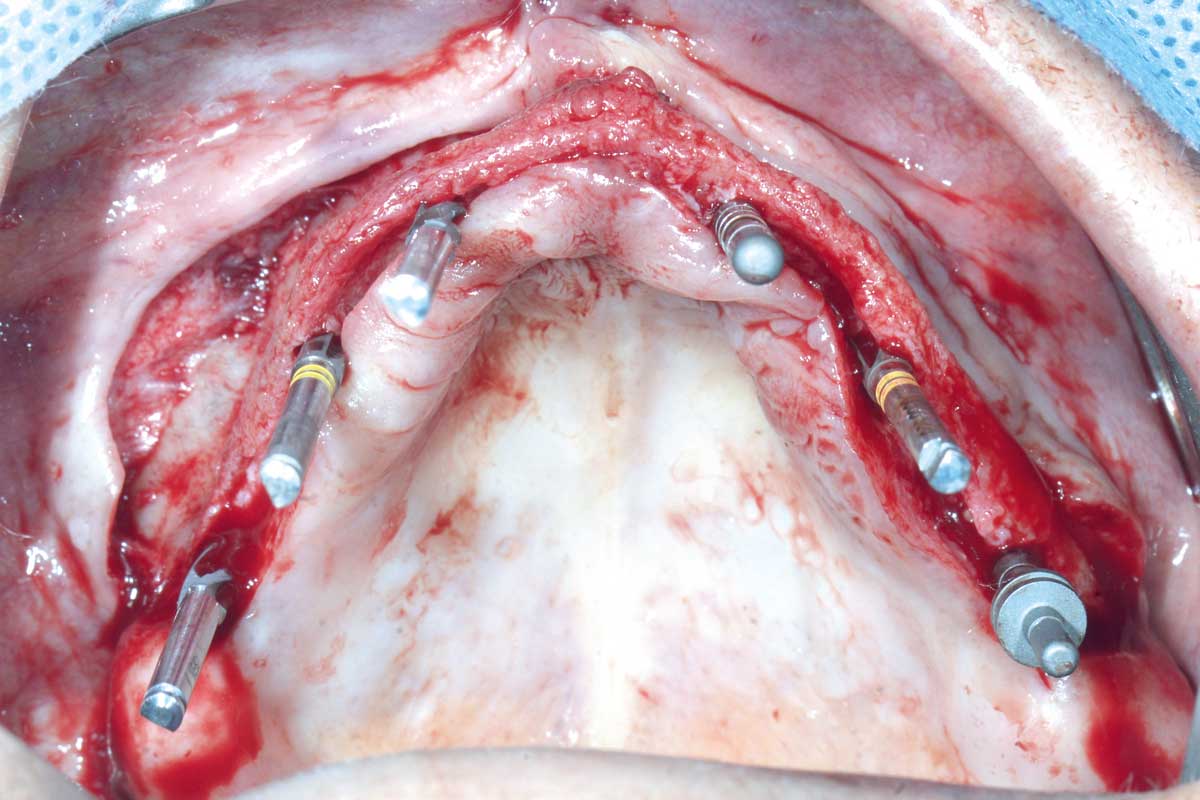

Full arch GBR using cerabone®, maxgraft® and Jason® membrane with simultaneous implantation of 6 Straumann® implants - Dres. A. Signorio and G. Molina